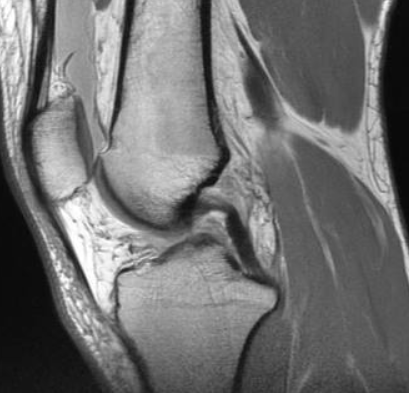

그리고 내년부터는 보장성강화를 위해 건강보험공단에서 복부 및 다른 부위에도 MRI 적용을 위해 제도 개선을 실시 중이라고 합니다.